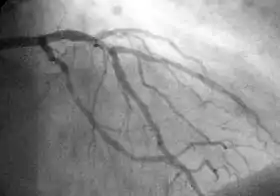

A coronary angiogram showing the circulation in the left coronary artery and its branches.